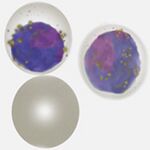

| Plasmodium malariae |

Brief summary

- Small rings (less delicate than P.falciparum) and becoming elongated or solid as parasites mature

- Red cells often small remaining a round shape and with no added dots unless heavily stained

- All forms tend to circulate, characteristically look for "daisy" schizonts and small round gametocytes

- Parasite number is often low